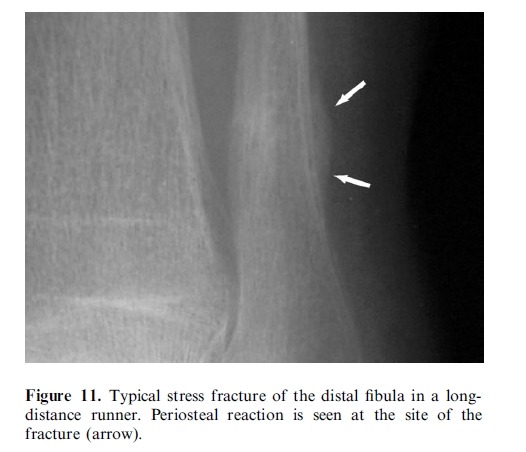

Imaging plays a major role in the management of ankle and foot problems. Most conditions are assessed by plain

films alone. MRI is an excellent technique for those cases where the diagnosis is uncertain as it can exclude most

clinically relevant pathologies. Ultrasound is an excellent tool for imaging focal soft tissue abnormalities. CT is

occasionally useful when bony detail is required. Bone scintigraphy has a limited role and has been largely replaced by MRI in many centres. The main reasons for referral are swelling and pain. Many conditions of the ankle and foot are related acute or repetitive trauma.